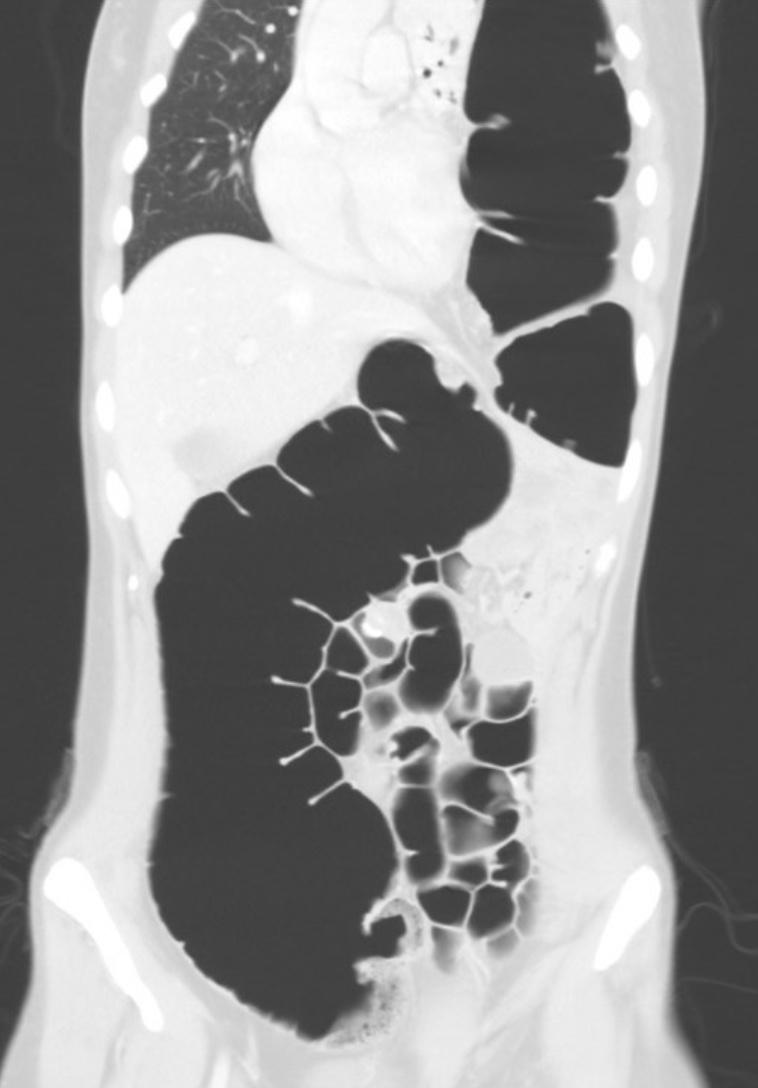

Gepubliceerd: Week 47 - 2024 920 deelnemers Een 28-jarige vrouw krijgt hevige buikpijn, drie maanden na een Nissen-fundoplicatie. Er is geen peritoneale prikkeling. De CT-scan laat een hyperlucent beeld zien. Wat is de diagnose? Antwoord pneumothorax bronchiale atresie ‘vanishing lung’-syndroom hernia diafragmatica Antwoord controleren